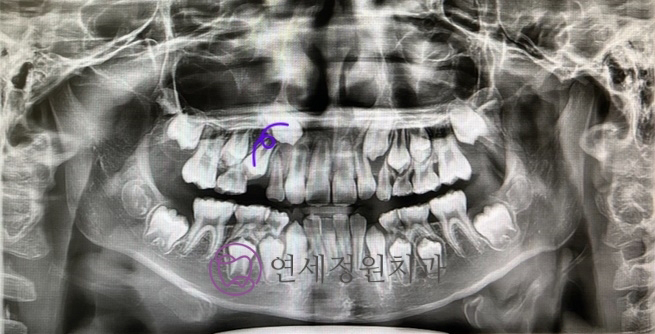

6개월 정도 후에 찍은 파노라마 사진인데, 뒤로 많이 기울어졌던 작은 어금니의 맹출 각도가 많이 개선된 것을 볼 수 있습니다. 이후로도 거의 1년 정도 장치는 꾸준히 착용하였고, 작은 어금니가 잇몸 바깥으로 뿅 하고 나오고 나서야 장치 착용을 멈췄습니다 :)

얼마 전에 찍은 파노라마인데, 아직 그 부위 송곳니는 다 맹출하진 않았지만 맹출 각도가 양호해진 것을 확인할 수 있습니다.